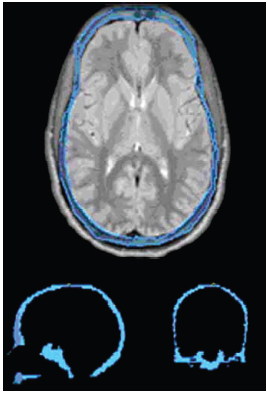

A New Improved Method for Assessing Brain Deformation after Decompressive Craniectomy

Publication: PLoS One. 2014 Oct 10;9(10):e110408. PMID: 25303305 | PDF Authors: Fletcher TL, Kolias AG, Hutchinson PJ, Sutcliffe MP. Institution: Department of Engineering, University of Cambridge, Cambridge, UK. Background/Purpose: Decompressive craniectomy (DC) is a surgical intervention used following traumatic brain injury to prevent or alleviate raised intracranial pressure. However the clinical effectiveness of the intervention remains in doubt. The location of the craniectomy (unilateral or bifrontal) might be expected to change the brain deformation associated with the operation and hence the clinical outcome. As existing methods for assessing brain deformation have several limitations, we sought to develop and validate a new improved method. Funding: